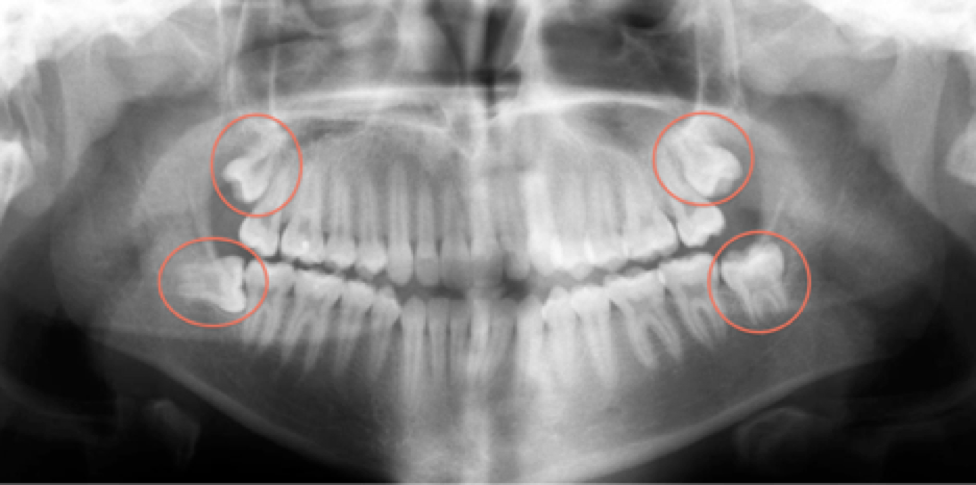

These late-blooming teeth can cause crowding, pain, and even damage to adjacent teeth if there’s not enough room in your child’s mouth. In some cases, wisdom teeth can become impacted, meaning they’re trapped below the gum line and unable to fully emerge. This can lead to painful infections, cysts, or damage to neighboring teeth and bone.

Early removal of wisdom teeth is often recommended to prevent potential complications. When a wisdom tooth becomes impacted, it can lead to various issues such as infection, damage to adjacent teeth, and cyst formation. An impacted wisdom tooth, which does not fully emerge due to space limitations or positioning within the jaw, may require surgical removal. This procedure can be more complex and involve an extended recovery time compared to a straightforward extraction. By addressing these issues early, patients can avoid the more severe complications associated with impacted wisdom teeth.

One common reason for early removal is the presence of impacted wisdom teeth, which can cause infection or damage to other teeth. Dr. Brett Habijanac, another experienced oral surgeon, explains, “Impacted wisdom teeth are like ticking time bombs—they may not cause pain immediately, but they can lead to serious issues if left untreated.”